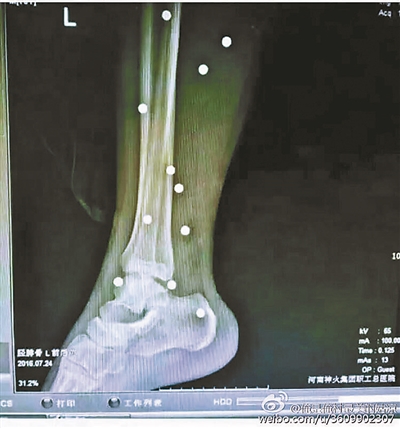

傷者體內(nèi)取出的鋼珠

爆炸導(dǎo)致鋼珠遍布傷者身體各處

黃明的伯伯對北青報記者表示,由于黃明直接踩到了爆炸物,所以傷情最為嚴重,“他的腿被炸斷,身體內(nèi)被炸進了40多顆鋼珠。手術(shù)后已經(jīng)從體內(nèi)取出29顆鋼珠,還有十多顆鋼珠沒有取出來。”根據(jù)黃明的入院記錄,他全身有多處爆炸傷,且全身多處異物存留。

爆炸發(fā)生時,陳浩的位置與黃明靠得很近,因此也受傷較重。他告訴北青報記者,經(jīng)過10多個小時的手術(shù)后,醫(yī)生從他身體里取出了12顆鋼珠。目前,他和黃明兩人經(jīng)過手術(shù)后,已從重癥監(jiān)護室轉(zhuǎn)至普通病房。其余三人中,陳剛的臀部受傷,當天晚上在醫(yī)院清理完傷口后便回了家,而同行的兩名女生身上有一些擦傷。